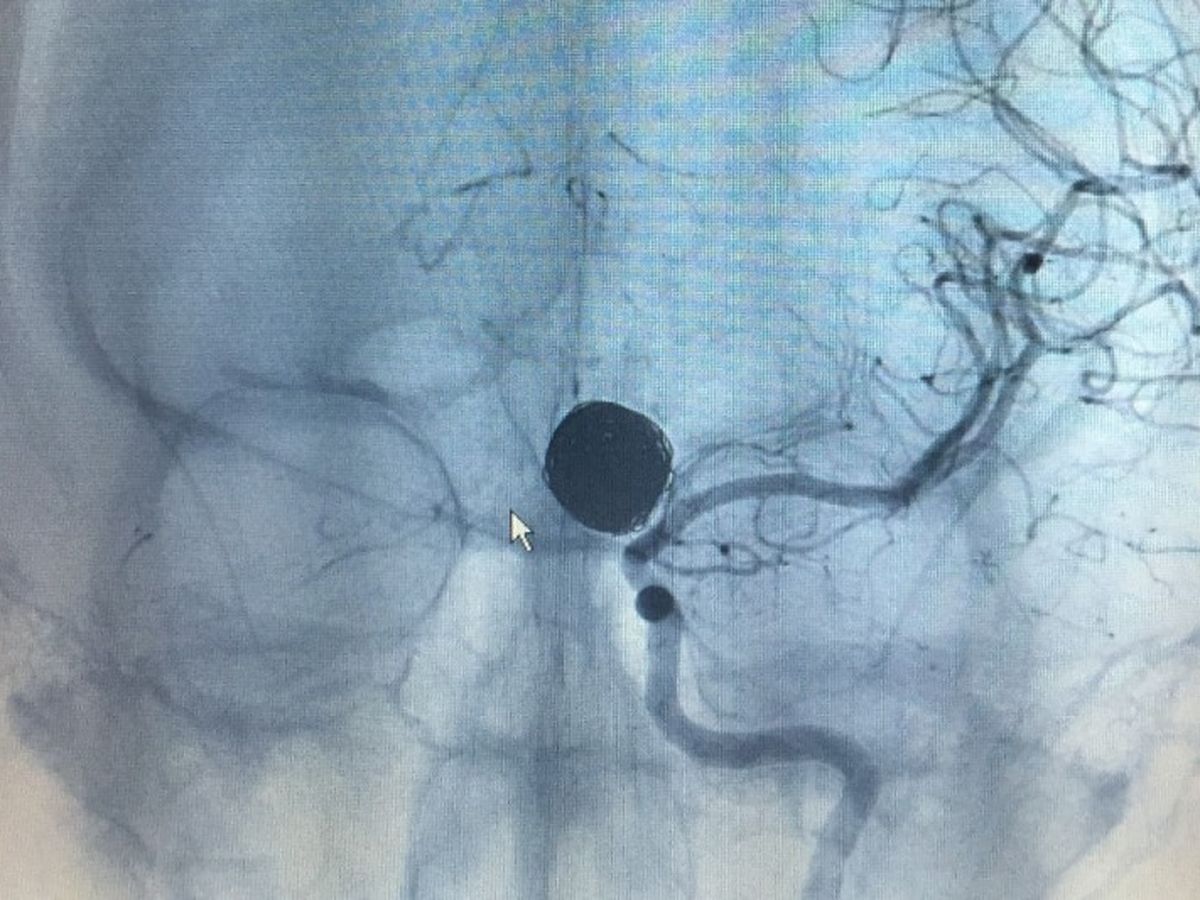

Late evening, on December 13, 2014 my 23 year old, pregnant daughter suffered a ruptured brain aneurysm in Saint Marys, GA. The ambulance took her to Camden County Hospital emergency room for CAT scan. Savannah was then immediately life-flighted to a Neuro Specialty Surgical Center at Baptist Hospital in FL, where she spent 12 days in ICU following brain surgery. Discharged from the hospital on Christmas Day, Savannah's recovery has been miraculous, with no permanent mental or physical damage. She and her husband, Kevin had just purchased their first home together in October 2014. The medical bills are begininning to pile in. As a young married couple with a one year old son and a baby girl on the way, the Steele family could really use some financial assistance for expenses not covered by their insurance. Please consider giving to our Christmas Miracle.